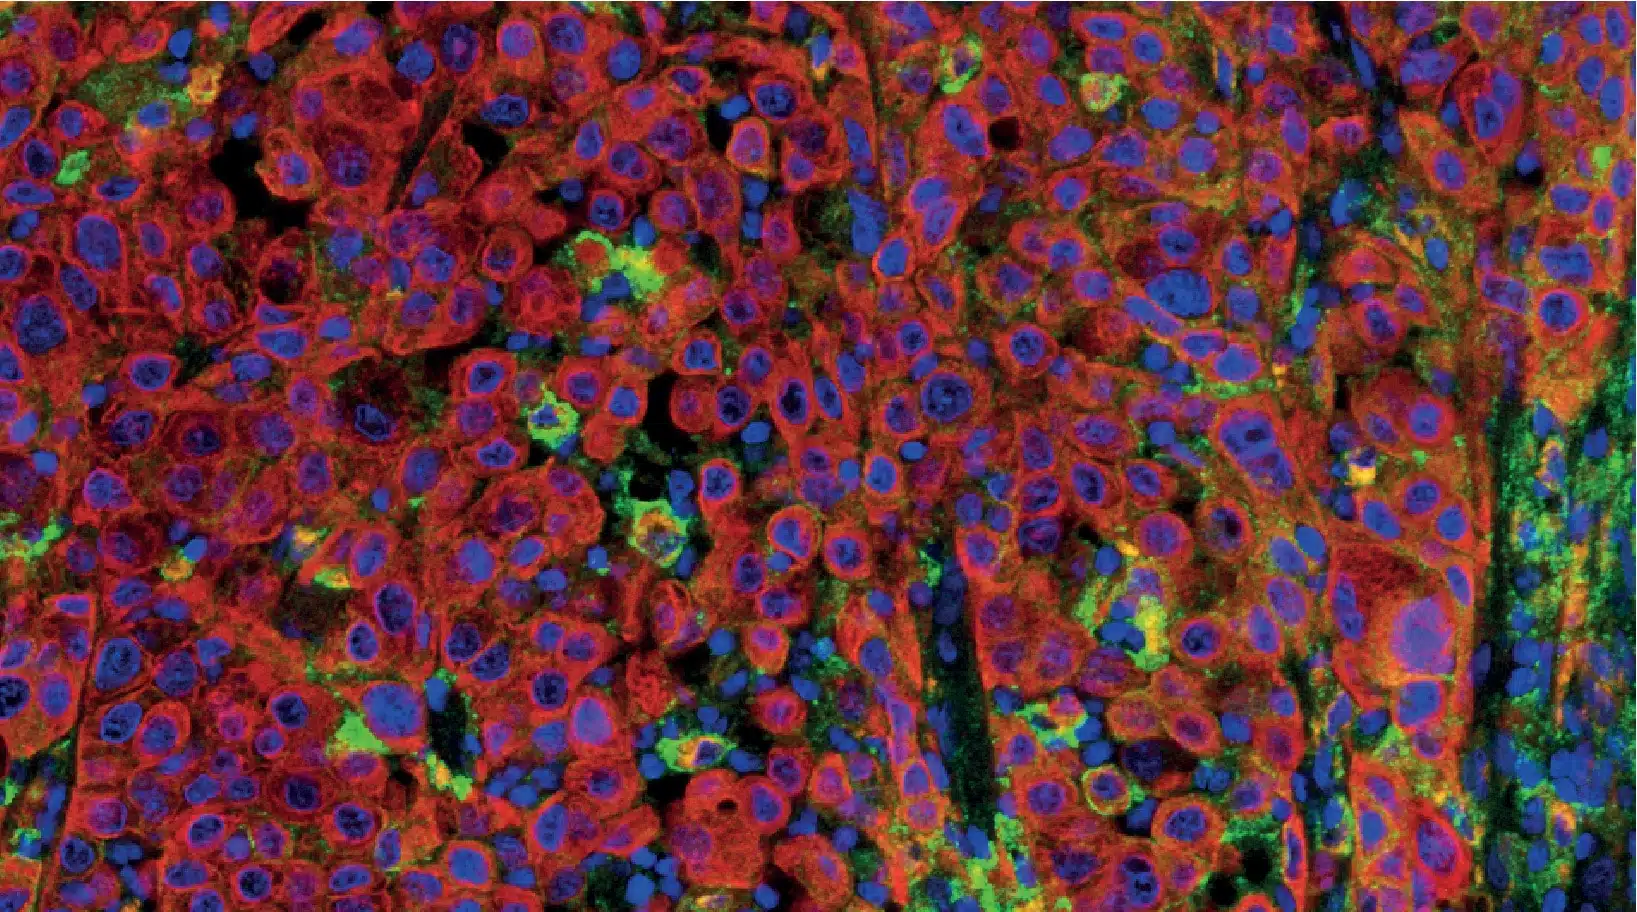

HBRI HISTOPROFILE® Multiplex IHC panels

HBRI offers both custom multiplex development and validation, as well as panels that come already validated for specific indications.

- Tissue resident memory T-Cells CD8/CD49a/CD3/CD68/CD103

- Dendritic cells langerin/CD1a

- T-cell activation CD8/Ki-67/GranzymeB

- T-reg Light CD3/CD8/FoxP3

- PD-L1 CD68/panCK/PD-L1

- Checkpoint inhibitors CD3/CD8/PD-1/PD-L1/Custom

- Neuro macrophage CD68/CD163/GFAP/TMEM-119/c-maf